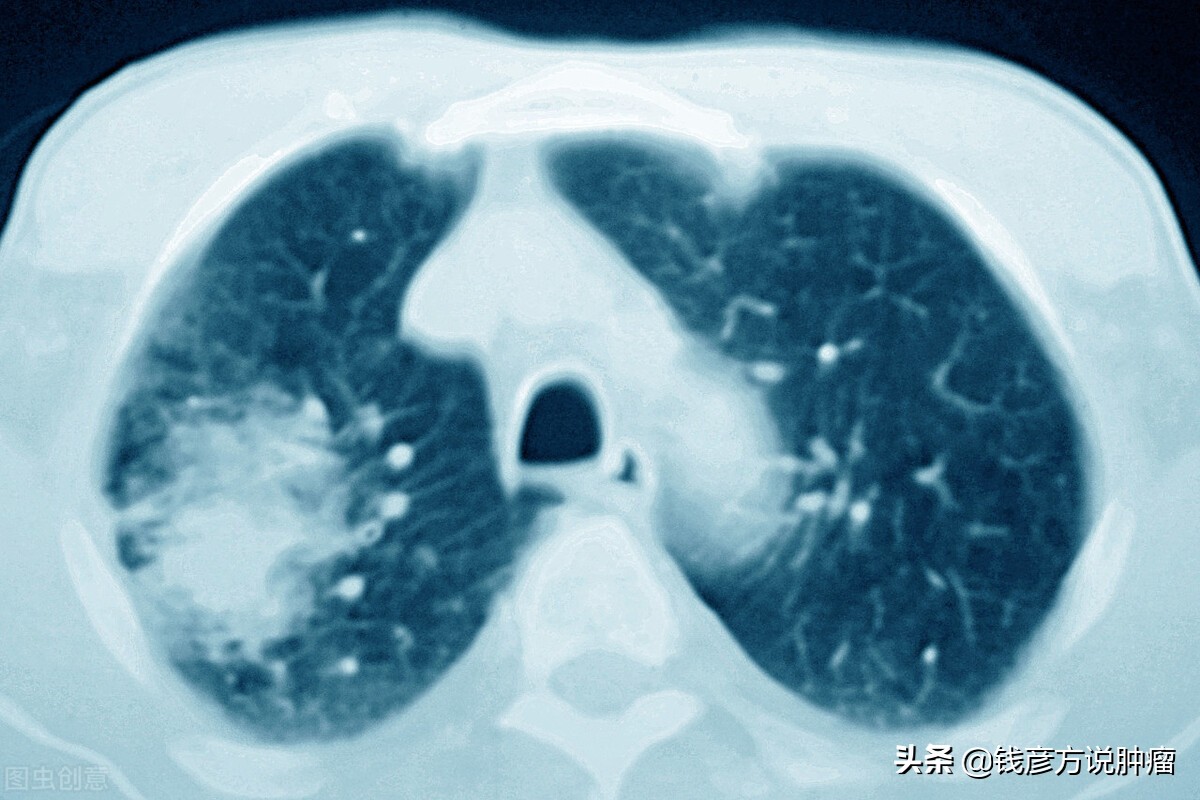

但是大概在手术后过了两年的时候,做了一次例行检查,就在她肺的对侧发现了一个阴影,这个阴影大概5毫米左右,对于一个术后肺癌患者来说,如果发现了肺部对侧再次出现阴影,首先考虑到复发和转移,当地的外科医生看了以后,也表示应该是复发,然后医生就说还要考虑一些化疗,做一些局部治疗,但是第一次化疗的时候没法耐受,然后就放弃了,继续下定决心吃中药。

然后就跟她说,咱们还是继续中药治疗,不论是复发还是转移,总之是有阴影存在的,继续用药的同时改变了一些策略,在原来的化痰润肺、活血消痰的基础上,我们不妨重用一些虫类药,把蜈蚣、全蝎加了上去,就这样治疗3~4个月的时间,肺部对侧的阴影就消失了。